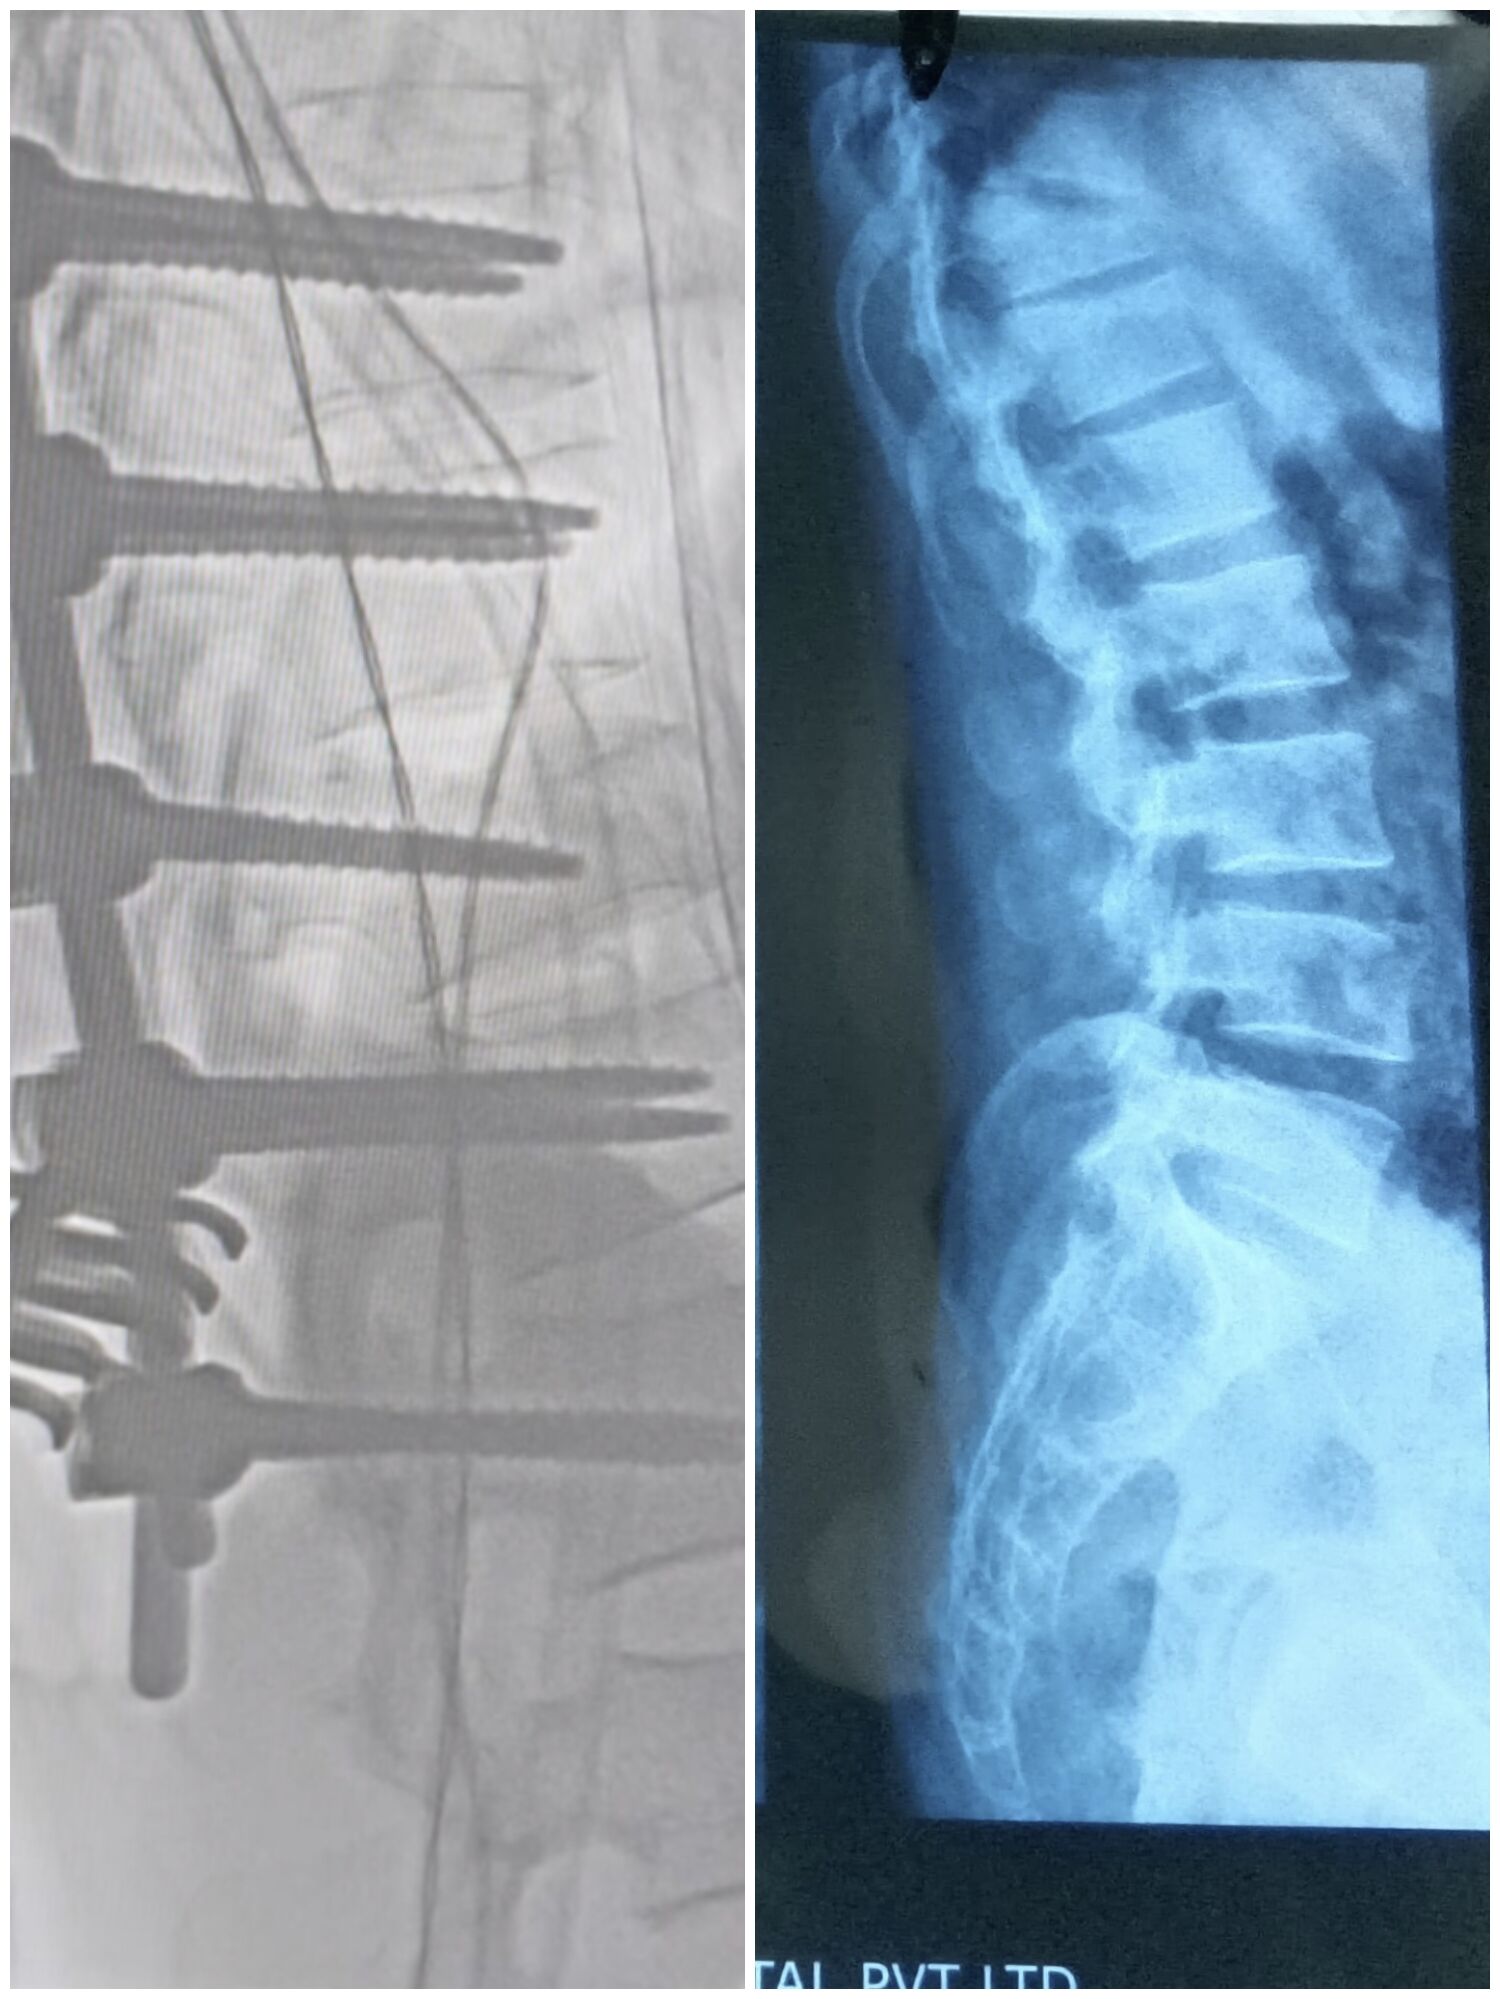

A thorough clinical examination and spinal imaging revealed the true extent of his injury: a D11 fracture with mild spinal cord compression.

Recognizing the need for urgent intervention, Dr. Mustafa ಚಾಂದಶಾ performed a posterior spinal fixation from D9 to L1.

The surgery stabilized the spine, corrected the deformity, and relieved pressure on the spinal cord.